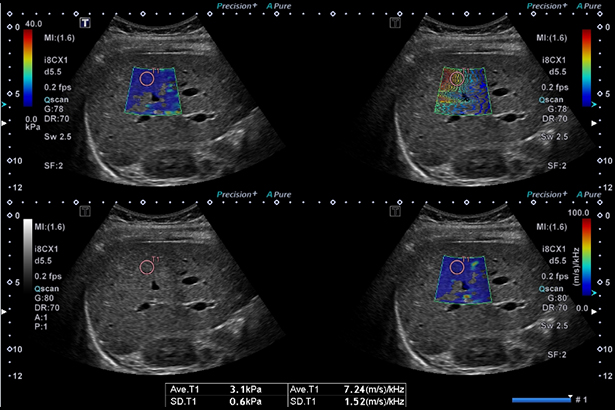

通過分析剪切波的每個頻率分量的傳播速度的變化,可以估計組織的黏度。黏度評估有望應用于肝病的早期和全面診斷。可以與剪切波彈性成像同時獲得,并且可以同時顯示任意 ROI 下測量的結果。通過四個畫面,可以同時觀察和測量 SWE,SWD,ATI 和傳播圖。

除了 SWE,SWD 和 ATI 的結果外,還可以在工作表中列出生化信息以及身高體重等任何信息,這是一個綜合報告功能,可以清楚地列出雷達圖表和滑塊顯示等信息。